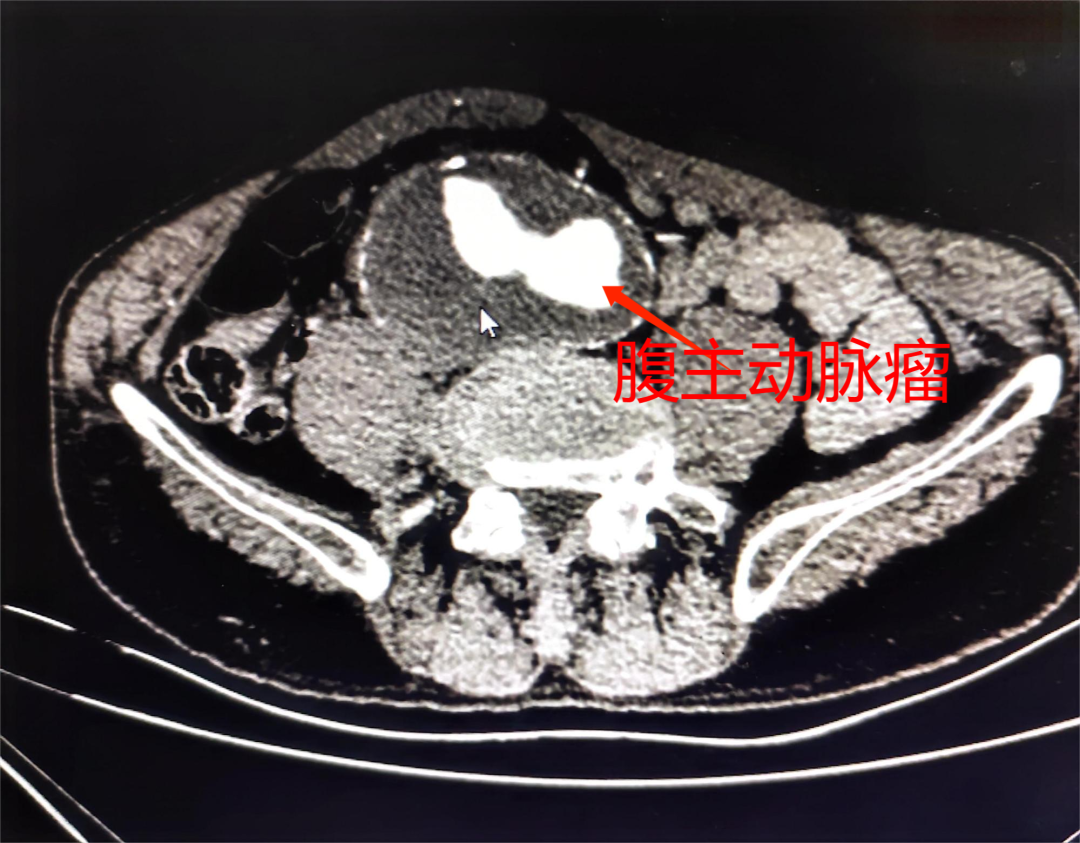

余先生,男,69岁,有高血压病史且长期便秘,脐周可处理一可搏动性包块,自认为是干结大便,直到近日,就诊于我院时,通过主动脉全程CTA发现,余先生腹部可搏动的包块,竟然是一颗巨大的腹主动脉瘤。主动脉是人体最粗的血管,如果那里发生病变鼓起了“包”,且超过正常血管直径的50%,就形成了人体不定时“炸弹”——主动脉瘤,一旦破裂随时危及生命,死亡率高达90%以上。